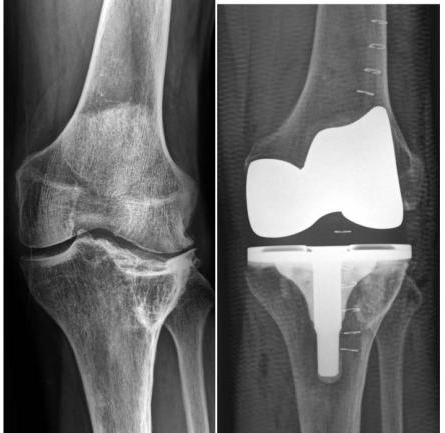

Por primera vez en América Latina se hizo un implante de prótesis anatómica de rodilla, un procedimiento médico de avanzada tecnología que llevó a cabo la Clínica FOSCAL.

Aunque el remplazo de rodilla es una intervención quirúrgica que se practica hace más de 50 años en el mundo, solo hasta hace unos cuantos días se logró hacer un implante completamente anatómico en América Latina, una técnica que hoy se realiza solo en algunas ciudades de Estados Unidos y Europa.

La Clínica FOSCAL Internacional se convirtió en la primera institución médica en Latinoamérica que implanta una prótesis anatómica de rodilla, un procedimiento de última tecnología que les permite a los pacientes recobrar el rango total de movimiento.

“Esta prótesis es completamente anatómica, eliminando así el proceso de adaptación y permitiendo una mas rápida rehabilitación, mejor resultado en la sensación de marcha del paciente y un arco de movimiento más amplio que favorece el uso de escaleras y de posiciones extremas de la rodilla, que son requeridas en algunas actividades de la vida diaria”, señaló Martínez Villalba.

“Como primer paso, las superficies del cartílago dañado en los extremos del fémur y la tibia se remueven junto con una pequeña cantidad del hueso subyacente, luego el cartílago y el hueso removidos son reemplazados con componentes metálicos que recrean la superficie de la articulación, después la superficie debajo de la rótula se corta y se resuperficializa con un botón de plástico, y por último se inserta en espaciador plástico de uso médico”, detalló Martínez Villalba.